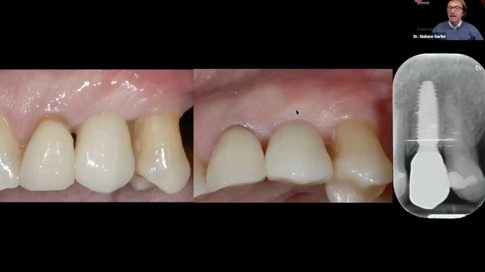

How and when to manage the soft tissue in the esthetic area - Part 2

Dr. Giuliano Garlini